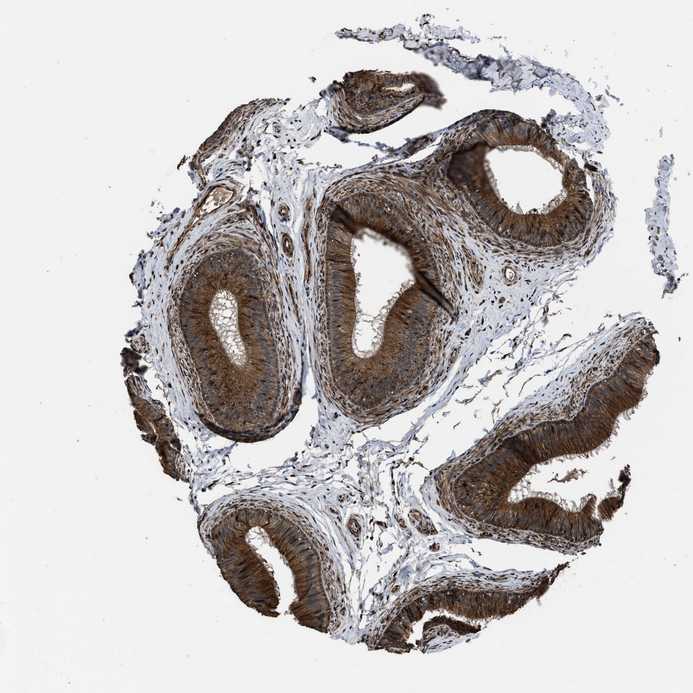

EPIDIDYMIS